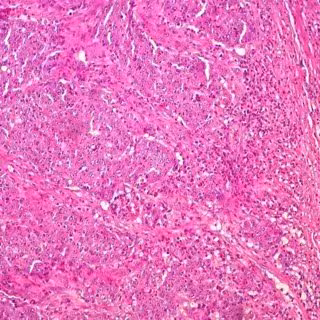

La vía de señalización Wnt, implicada en el cáncer colorrectal

Lieu y su equipo trabajaron con la Fundación de Medicina para analizar la genética de 4.699 muestras de tejido de CRC. A continuación, el equipo exploró las diferencias genéticas entre las muestras que habían sido tomadas de pacientes mayores y menores de 50 años de edad. A pesar de que los cánceres de los pacientes más jóvenes y mayores comparten muchos de los mismos cambios genéticos, los de los más jóvenes eran más propensos a tener alteraciones en los genes CTNNB1 y FAM123B, que son jugadores importantes en el sistema más grande conocido como vía de señalización Wnt.